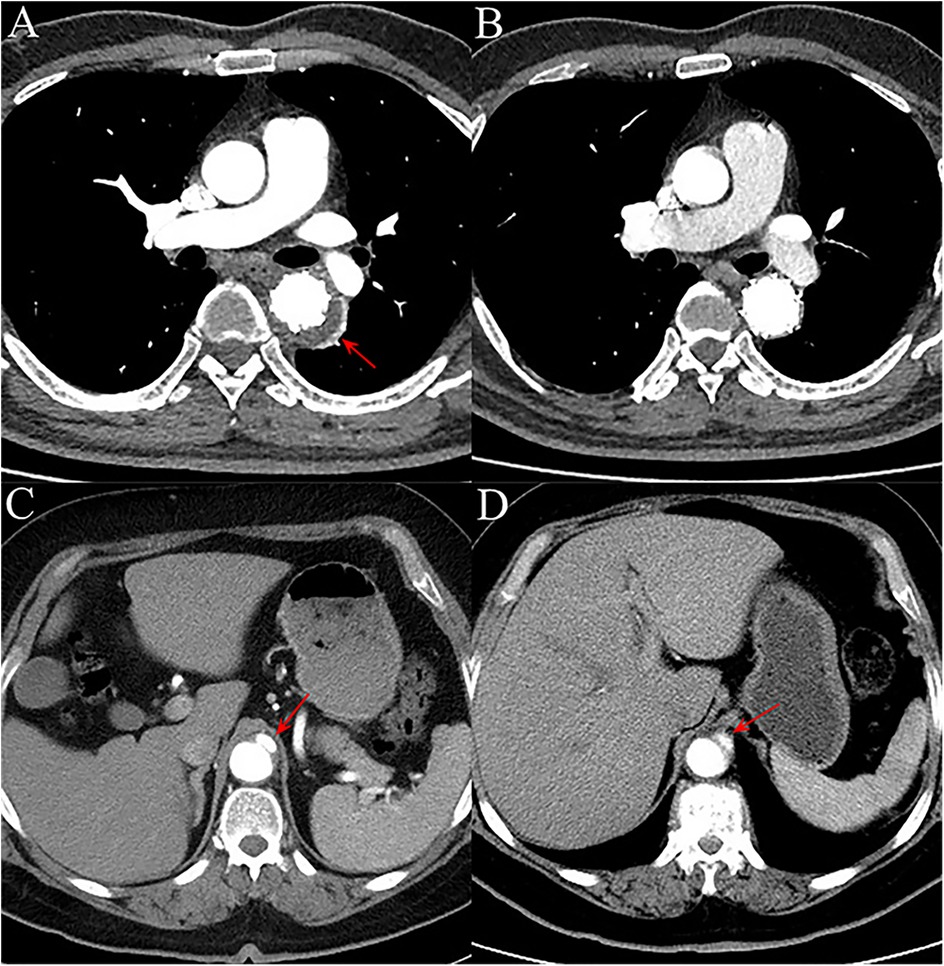

Objective: Thoracic endovascular aortic repair (TEVAR) is increasingly performed in patients with acute type B intramural hematoma (IMH). This study aimed to evaluate the effect of diabetes mellitus (DM) on postoperative clinical outcomes and aortic remodeling degree of acute type B IMH patients undergoing endovascular repair. Methods: We retrospectively identified patients diagnosed with acute type B IMH at two medical centers between January 2017 and January 2024. Study subjects were divided into DM and none DM (nDM) groups. Baseline characteristics, procedure details, and postoperative outcomes were extracted for further analysis. Results: Forty-four patients were included in the study and were divided into DM (n=12) and nDM groups (n=32). Preoperative demographic characteristics, laboratory biomarkers, and imaging data were similar between the two groups. Compared with nDM group, the DM group presented a slightly higher rate of patients without postoperative major adverse events (MAE) (75.0% vs 68.8%, p = 0.651). At the 1-year follow-up, the DM group exhibited a significantly higher degree of aortic remodeling, as assessed by the TAD/TLD ratio (total aortic diameter [TAD] divided by the true lumen diameter [TLD] at the maximal IMH thickness) (DM group: 1.09 ± 0.04; nDM group: 1.17 ± 0.10, p = 0.032). Cox multivariate regression revealed that a TAD/TLD ratio > 1.32 increased the incidence of postoperative MAE significantly. Conclusions: DM is positively associated with the prognosis of patients with acute type B IMH undergoing TEVAR and promotes postoperative aortic remodeling. Moreover, a TAD/TLD ratio > 1.32 independently predicts the incidence of